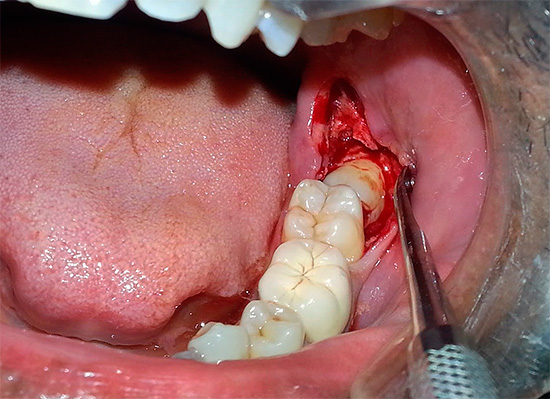

- o grande volume e a invasão da próxima intervenção cirúrgica (por exemplo, através de raios-x, às vezes você pode antecipar a remoção complexa de dentes do siso com antecedência);

Em segundo lugar, o paciente, imerso em sono profundo, não pode seguir as instruções do médico, tornando seu trabalho mais conveniente (pelo menos básico para abrir mais a boca para que haja melhor acesso ao dente problemático). Portanto, o médico é forçado a mudar constantemente a posição do seu corpo para reduzir a carga nos músculos, o que leva à fadiga rápida. Mas todos entendemos que, por exemplo, com uma remoção longa e difícil de um dente do siso, a fadiga do médico não aumentará seu trabalho de qualidade: em algum lugar sua atenção diminuirá, em algum lugar ele poderá escolher uma opção mais rápida e fácil, mas também mais traumática para o procedimento. . Existem muitas oportunidades ...

- A capacidade de realizar operações longas e complexas para remover um ou mais dentes, especialmente nos casos em que os dentes têm uma estrutura complexa e uma posição incorreta na mandíbula. Isto é especialmente verdade. ao remover os dentes inferiores da sabedoria, uma vez que a estrutura e a localização desses dentes na mandíbula são absolutamente imprevisíveis.